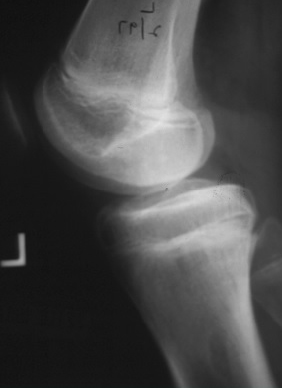

[Figure caption and citation for the preceding image starts]: Healed osteochondritis dissecansFrom the collection of H. Chambers, MD [Citation ends].